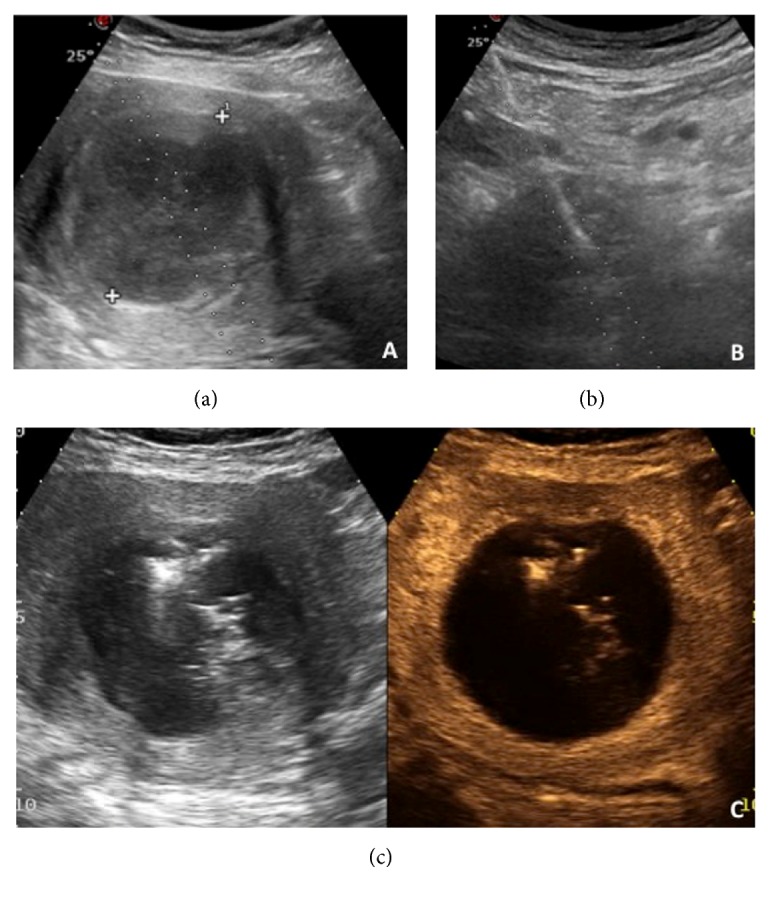

多发性子宫肌瘤微波消融核磁复查

子宫肌瘤微波消融肌瘤坏死的黑洞